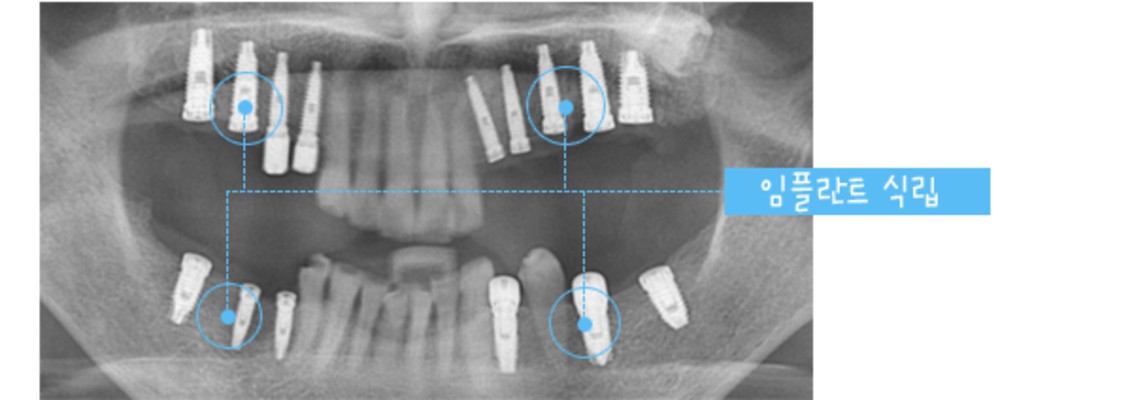

▶ 상악과 하악의 명확한 교합을 위해 적정한 각도로 임플란트를 식립하여 정교하고 강도 높은 보철 제작으로 실제 사용 시 불편함을 제거합니다.

▶ 3D CT를 통한 정밀 검사와 리뷰로 관리 계획을 세우고 관리하여 관리 시 손실이나 응급 사태에 대한 우려 없이 만족적인 임플란트 관리가 가능합니다. 뿐만 아니라 조직 손실이 매우 적어 복원과 재활이 매우 빠릅니다.

기존 임플란트 방식인 절제가 아닌 무절제 (미세 절제)를 활용하여 출혈이나 부기의 우려가 적으며 염의 가능성이 크지 않아 빠른 일상 복원이 가능한 네비게이션 원리 임플란트는 관리 전 컴퓨터로 가상 관리를 시행하여 임플란트 위치를 결정해 미리 심어볼 수 있는 가이드 입니다.

임플란트의 안정성과 식립률을 높일 수 있는 방법이며 당뇨, 고혈압, 아픔에 대한 두려움을 가지고 있는 분들도 부담 없이 임플란트 심기가 가능합니다.